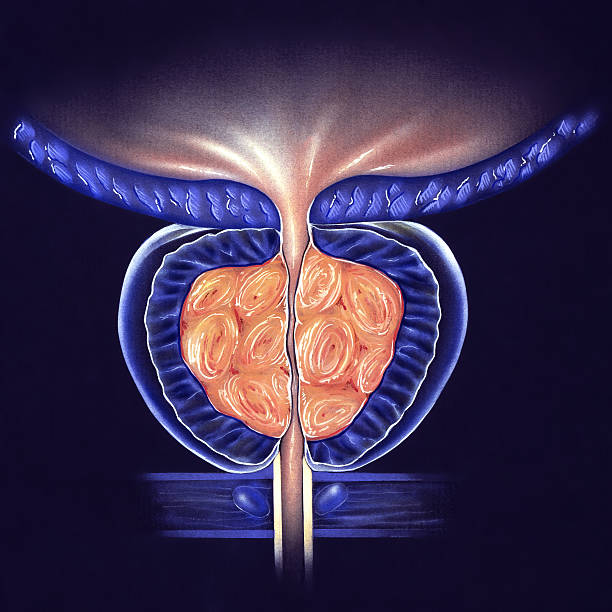

남성 생식기의 요로계와 직접적 연관이 있는 전립선은 사과 모양으로 배꼽 아래쪽에 위치해 있으며 상당히 중요한 역할을 하고 있습니다. 전립선은 사정을 조절하고, 정자의 움직임을 돕는 전립선 분비액을 만들어냅니다. 이 분비액은 정자의 영양 공급과 이동에 필수적인 성분을 포함하고 있습니다. 또한, 전립선은 방광을 둘러싸고 있는 방광 경화근과 골반 바닥 근육에 대한 지지 구조 역할을 할 수 있어 상당히 중요하나 전립선에도 암이 발병될 수 있어 초기에 원활한 대응을 해야만 합니다. 그럼 이번 시간에는 전립선암 초기증상에 대해 자세히 정리해보겠습니다.